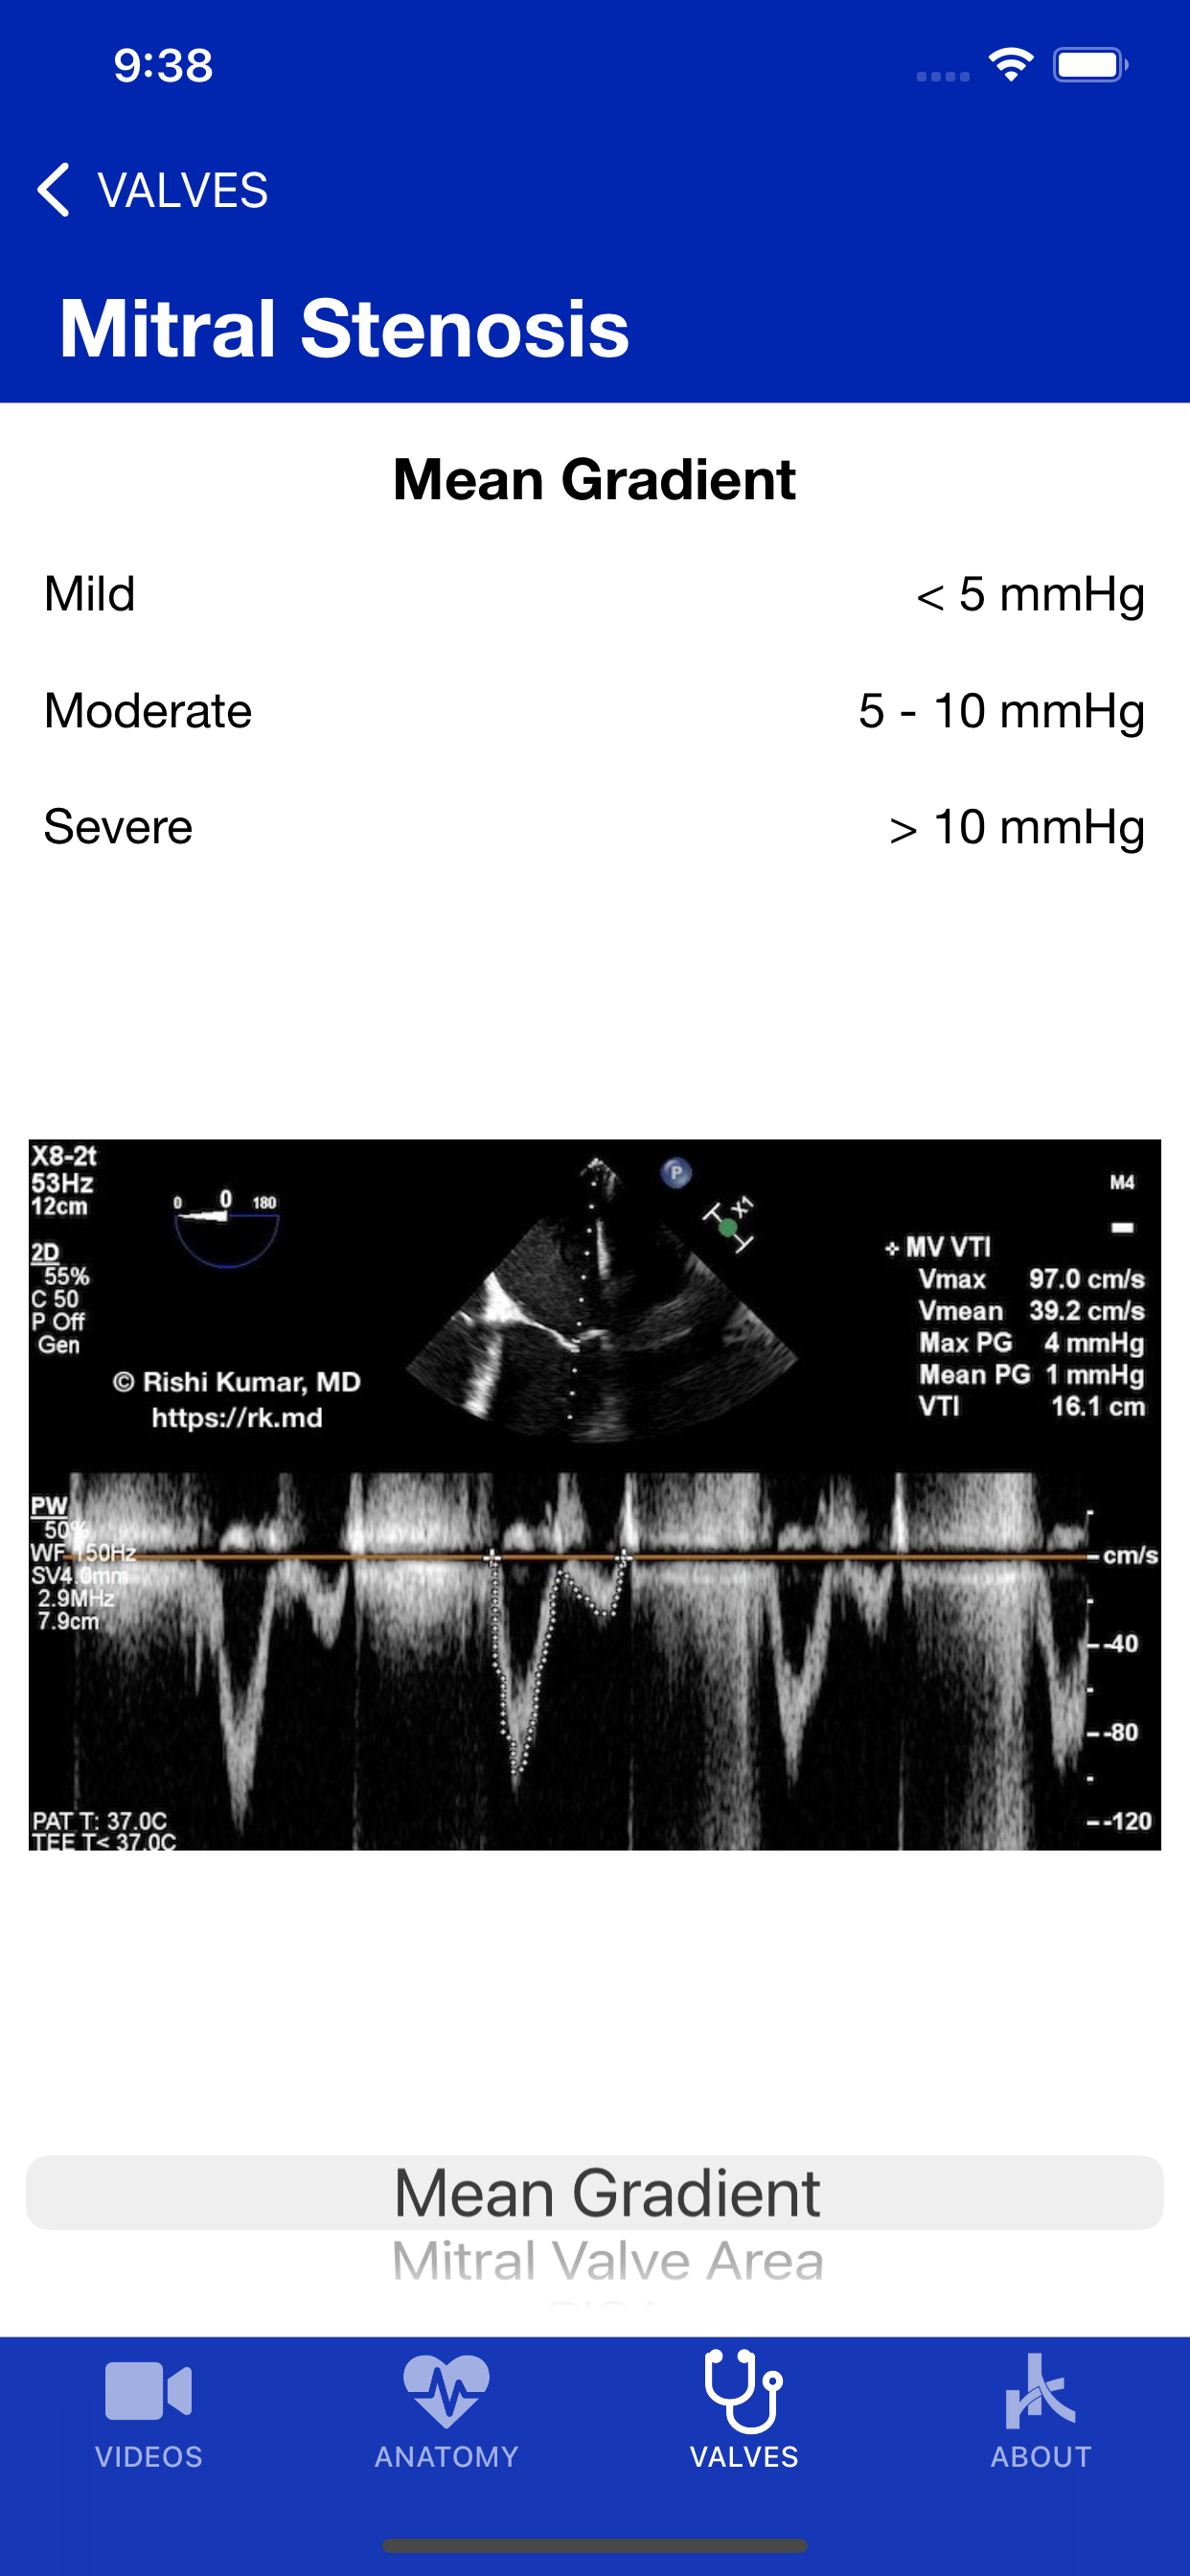

EchoTools is a free iOS educational reference with videos of point-of-care ultrasound (POCUS), transthoracic echocardiography (TTE), and transesophageal echocardiography (TEE). Additionally, it covers cardiac dimensions, native/prosthetic valve measurements, and lessons ranging from interventional procedures to mechanical circulatory support (MCS). About Rishi Kumar, MD, FACC ("RK.md"): I'm an adult cardiothoracic anesthesiologist and intensivist with board certifications in anesthesiology, critical care medicine, advanced perioperative transesophageal echocardiography (TEE), and a testamur in critical care ultrasound. I have a passion for teaching and free, open-access medical education over the Internet! Learn more on my site: https://rk.md